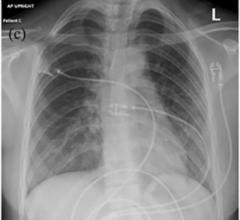

An example of a COVID-19 (SARS-CoV-2) pneumonia on chest computed tomography (CT) scan. Coronavirus appears as ground ...